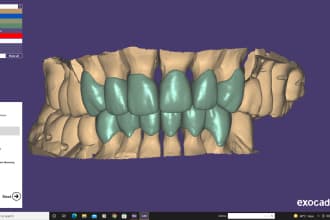

I will do dental prosthesis crown design using exocad, 3shape, inlab and cerec

From $20